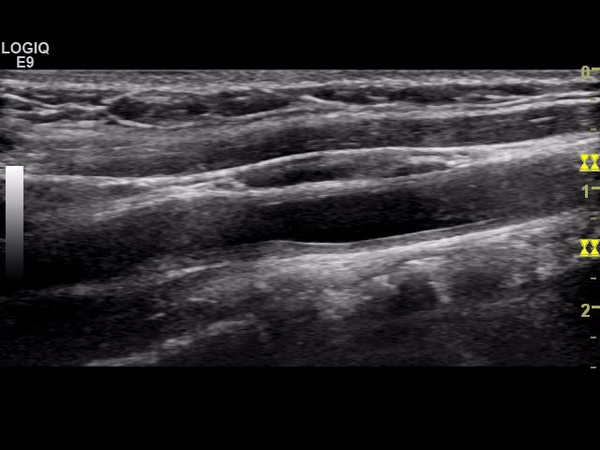

A 28 year old lady presented with transient left arm weakness. This had been preceded by a two month history of fever, malaise, generalized arthralgia and a more focal tenderness in her neck bilaterally. She described subtle weakness raising the possibility of a stroke.

Her investigations included a carotid Doppler (Figs 1, 2 shows grey scale and Doppler cineclips of the right common carotid artery/bulb).

Figure 1 |